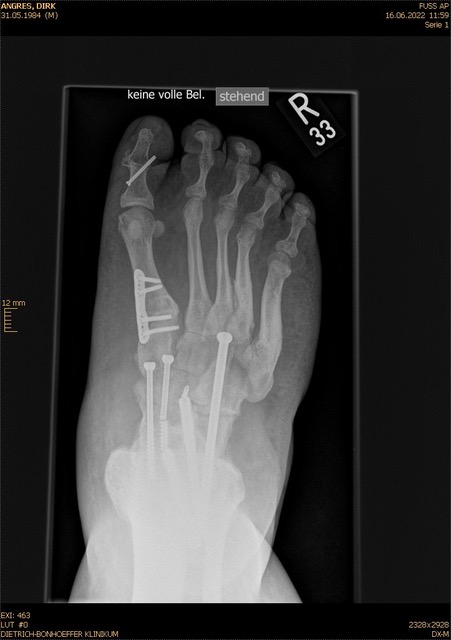

• Fuß belastet dp und seitlich (Abb. 14 und 15)

• Saltzman view (Abb. 16)

Typische Merkmale der Standard-dp-Röntgenaufnahme des Fußes im Stand

• Talus und Calcaneus verlaufen fast parallel

• Os naviculare ist gegenüber dem Talus nach medial gedrängt

• Metatarsalia überlappen sich basisnah

• Metatarsale I erscheint verkürzt

• Metatarsus adductus

Typische Merkmale der Standard-Seitaufnahme des Fußes im Stand

• Knöchelgabel ist außen rotiert

• Sinus tarsi ist einsehbar

• Subtalare Gelenklinie verläuft horizontal und ist breit einsehbar

• Der Abstand Malleolus medialis zum Os naviculare ist verkürzt

• Der Calcaneus erscheint verkürzt

• Der Krümmungsscheitel des Fußes ist erhöht

• Calcaneus pitch ist meist erhöht, der Rückfuß Equinus ist eher selten 12